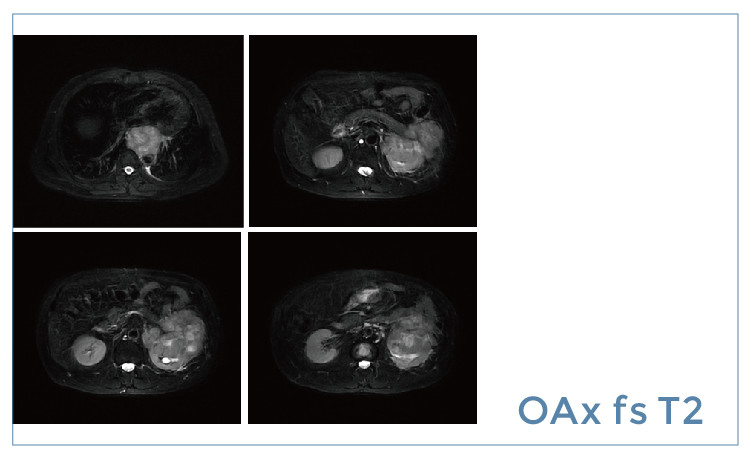

【朗润影像档案】20190426磁共振影像病例结果讨论

【朗润影像档案】磁共振影像病例分享(编号20190426)